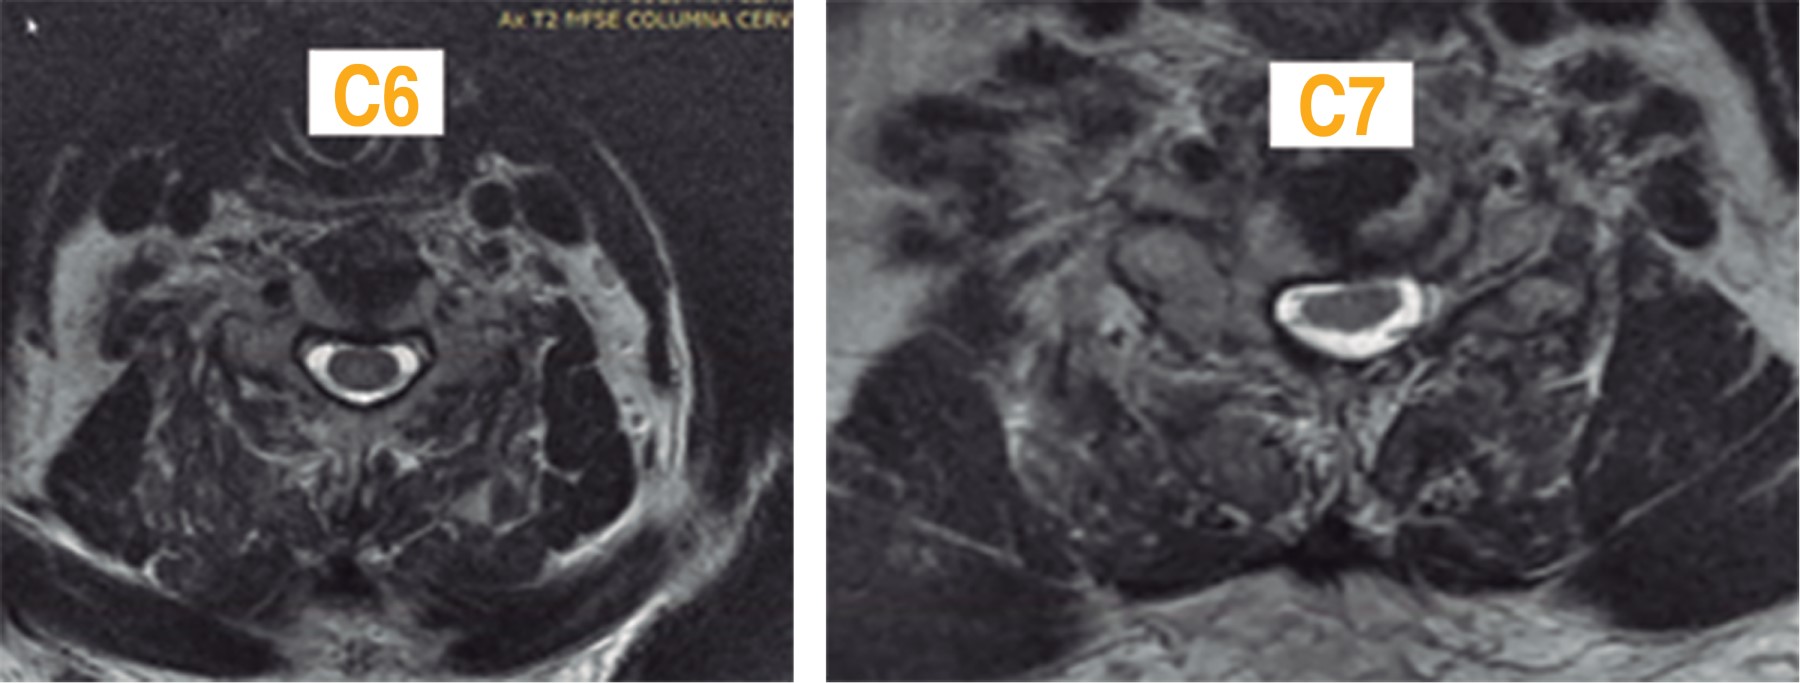

Figure 4

Figure 5